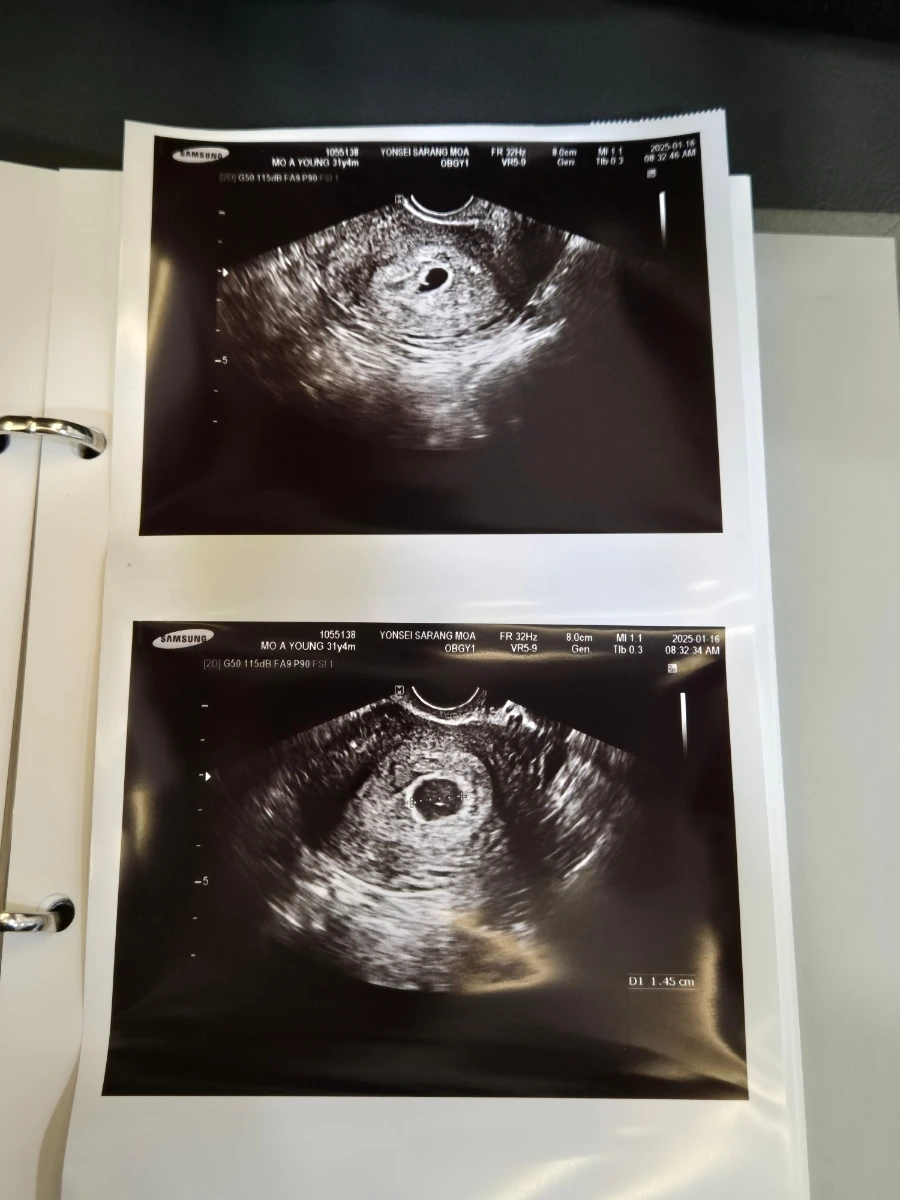

처음 산부인과를 찾던 날은 어찌나 걱정되고 떨렸는지 모르겠다. 임신이 아니었으려나, 아기집이 잘 안 보이면 어쩌지.. 온갖 잡생각을 안고 갔는데 다행히 좋은 위치에 잘 자리 잡고 있다는 소식을 듣고 안심했던 기억이 있다. 남편과 태명을 고민하기 시작했던 시기다.

우리 아기의 태명은 엄마의 닉네임인 알감자와 작은 콩처럼 소중하다는 뜻에서 '알콩이'라고 지었다. 이날은 처음으로 두근두근 알콩이의 심장소리를 확인한 날이었다. 내 뱃속에 생명이 자라고 있다는 실감이 났던 순간이었다. 아기의 심장박동수는 어른보다 조금 빠르다고 하셨다. 저 작은 것이 우렁차게 심장소리를 내는 것을 들으니 안심되고 참 감사한 하루였다.